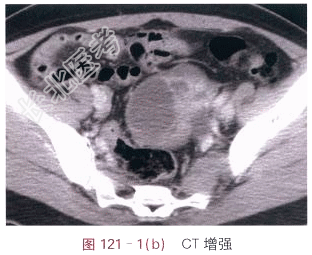

- [材料题] 患者,女,44岁,发现腹部包块2月余。体格检查:未见阳性体征。影像学资料如图121-1~图121-3所示。

- 简答题1、请叙述卵巢癌临床症状和该影像学表现?